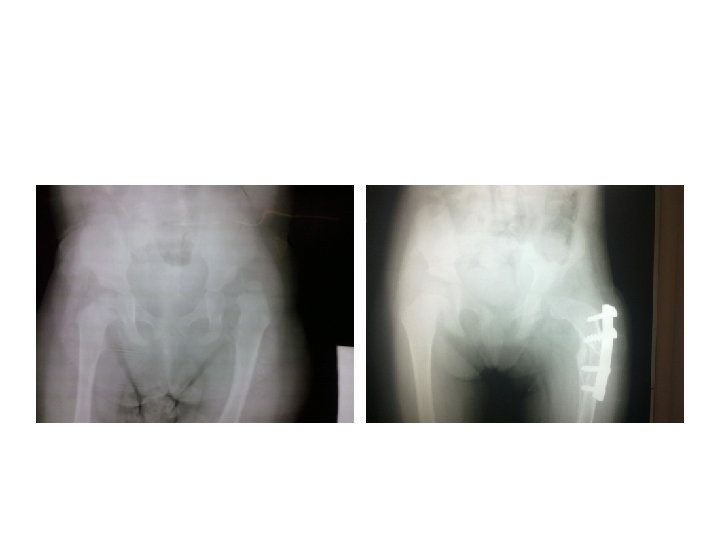

Somerville technique of anterior open reduction in congenital dislocation of hip. A, Bikini incision.

Somerville technique of anterior open reduction in congenital dislocation of hip. A, Bikini incision. B, Division of sartorius and rectus femoris tendons and iliac epiphysis. C, T-shaped incision of capsule. D, Capsulotomy of hip and use of ligamentum teres to find true acetabulum. E, Radial incisions in acetabular labrum and removal of all pulvinar from depth of true acetabulum. F, Reduction and capsulorrhaphy after excision of redundant capsule. G, Developmental dislocation of right hip. H, After anterolateral open reduction. I, At age 7 years; note remodeling of femoral head and acetabulum.

Guidelines for treatment of DDH in relation to age group Neonate: Place in Pavlik

Guidelines for treatment of DDH in relation to age group Neonate: Place in Pavlik harness splint for 6 weeks duration. 1 to 6 months: Place in Pavlik harness for 6 weeks after hip reduces by closed reduction. 6 to 18 months: skin traction; closed reduction. If closed reduction is successful, place in cast for 3 months. If closed reduction is unsuccessful, perform open reduction. 18 to 24 months: Trial of closed reduction, or open reduction. A Salter osteotomy may or may not be part of the procedure. 24 months to 6 years: primary open reduction and femoral shortening, with or without a Salter osteotomy.